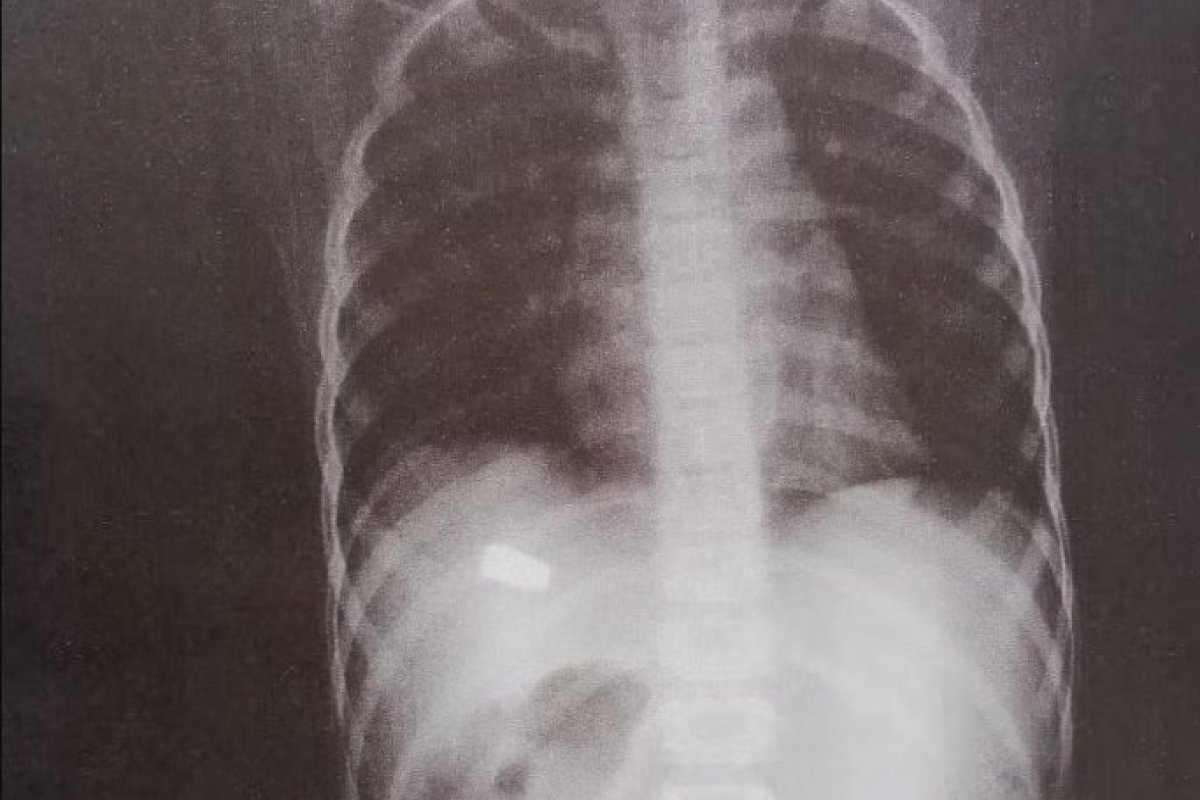

Uma criança de 8 anos foi atingida por um tiro enquanto brincava na casa da madrinha, no bairro de Mussurunga, em Salvador, no domingo (4). A família informou que o menino sentiu dor no abdômen e foi levado à Unidade de Pronto Atendimento (UPA) do bairro, onde um exame de raio-x revelou a lesão causada por disparo de arma de fogo.